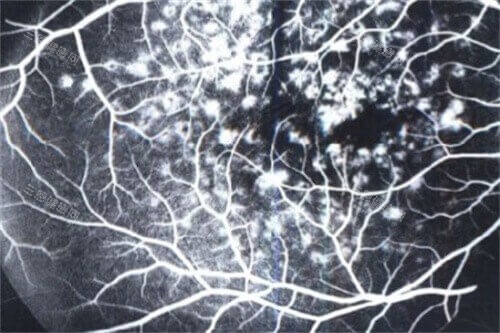

定期进行OCT与荧光素血管造影(FFA)检查,监测黄斑区结构变化。